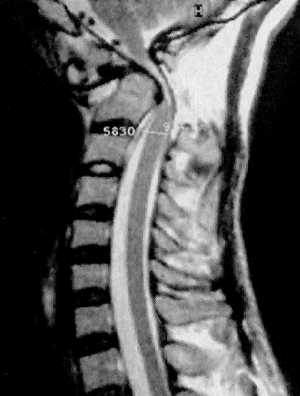

КТ и цифровая спондилография - важные методы диагностики вывихов атланта (рис.

1.7 и 1.8). МРТ позволяет определить не только дислокацию атланта, но и степень

компрессии спинного мозга (рис. 1.9).

|

Рис 1.7. Ротационный вывих атланта по

данным цифровой спондилографии |

Рис. 1.8. Вывих в атланто-аксиальном сочленении по данным

цифровой спондилографии |